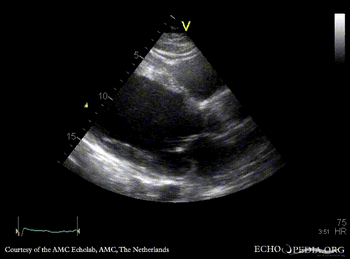

E00217.gif E00218.gif

PLAX: dilated left ventricle with poor function PSAX: dilated left ventricle with poor function, spontaneous echo contrast